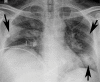

The coronavirus disease 2019 (COVID-19) pandemic is a global health care emergency. Although reverse-transcription polymerase chain reaction testing is the reference standard method to identify patients with COVID-19 infection, chest radiography and CT play a vital role in the detection and management of these patients. Prediction models for COVID-19 imaging are rapidly being developed to support medical decision making. However, inadequate availability of a diverse annotated data set has limited the performance and generalizability of existing models. To address this unmet need, the RSNA and Society of Thoracic Radiology collaborated to develop the RSNA International COVID-19 Open Radiology Database (RICORD). This database is the first multi-institutional, multinational, expert-annotated COVID-19 imaging data set. It is made freely available to the machine learning community as a research and educational resource for COVID-19 chest imaging. Pixel-level volumetric segmentation with clinical annotations was performed by thoracic radiology subspecialists for all COVID-19-positive thoracic CT scans. The labeling schema was coordinated with other international consensus panels and COVID-19 data annotation efforts, the European Society of Medical Imaging Informatics, the American College of Radiology, and the American Association of Physicists in Medicine. Study-level COVID-19 classification labels for chest radiographs were annotated by three radiologists, with majority vote adjudication by board-certified radiologists. RICORD consists of 240 thoracic CT scans and 1000 chest radiographs contributed from four international sites. It is anticipated that RICORD will ideally lead to prediction models that can demonstrate sustained performance across populations and health care systems.